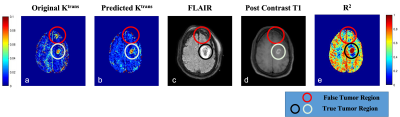

Figure 3 shows that the predicted Ktrans map shows the difference in the highlighted region which is cross-checked with FLAIR, Post Contrast T1 and R2 map, which confirms that the predicted Ktrans map is more accurate than the conventional Ktrans map, suggesting that the proposed network was good at picking the accurate and precise tumor regions and with reduced computation time.

The mismatch between the Ktrans map of predicted and actual (NLLS), shows how important the synthetic data was to establish a pre-trained network. This architecture has been trained and tested on HGG patients only (Figure 3). One of the limitations of the study is lack of true ground truth for experimental data. However, alternative approaches have been used for evaluating accuracy. In future, proposed framework will also be evaluated for other brain tumors data and from multiple centres.

Figure 3: Comparison of original (a) & predicted (b) Ktrans map with FLAIR (c), Post Contrast T1 (d) MRI and R2 maps(e) for identification of true tumor lesion